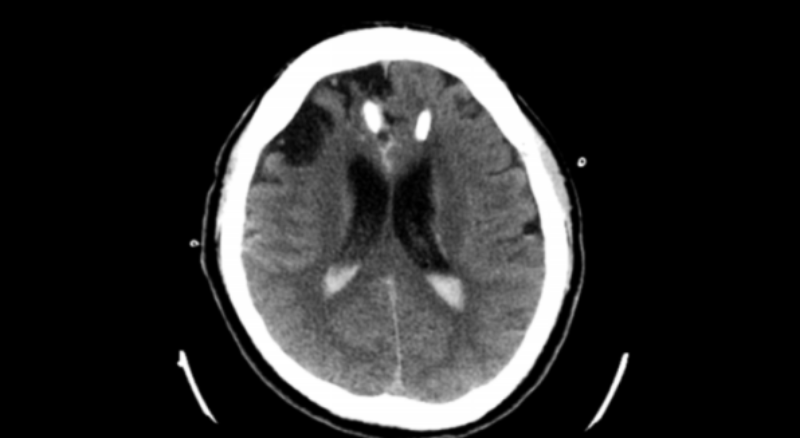

47 歲的張濤(化名)在工作的時候突然就失去意識,隨即撥打 120。來到惠州市中心人民醫(yī)院博羅分院(博羅縣人民醫(yī)院)急診醫(yī)學科,醫(yī)生給他接上呼吸機并進行了止血、補液等緊急處理,后經(jīng)查CT ,結(jié)果顯示是“丘腦出血”,而且還有血流進了腦室里,有腦積水的情況。經(jīng)醫(yī)生診斷為左側(cè)丘腦出血并破入腦室以及梗阻性腦積水。因為患者出血量比較大,還引起了腦積水,必須趕快想辦法把這個梗阻解除,不然容易出現(xiàn)腦疝?;葜菔兄行娜嗣襻t(yī)院派駐博羅分院主任醫(yī)師、博羅分院腦外科中心主任羅洪海帶領團隊迅速組織討論后,決定使用軟通道技術(shù)來處理是最合適的治療策略。于是神經(jīng)外科副主任戴兵和家屬溝通商量治療策略后,在床邊局麻下用軟通道技術(shù)為患者進行“雙側(cè)腦室錐顱置管引流術(shù)”。

入院CT-1